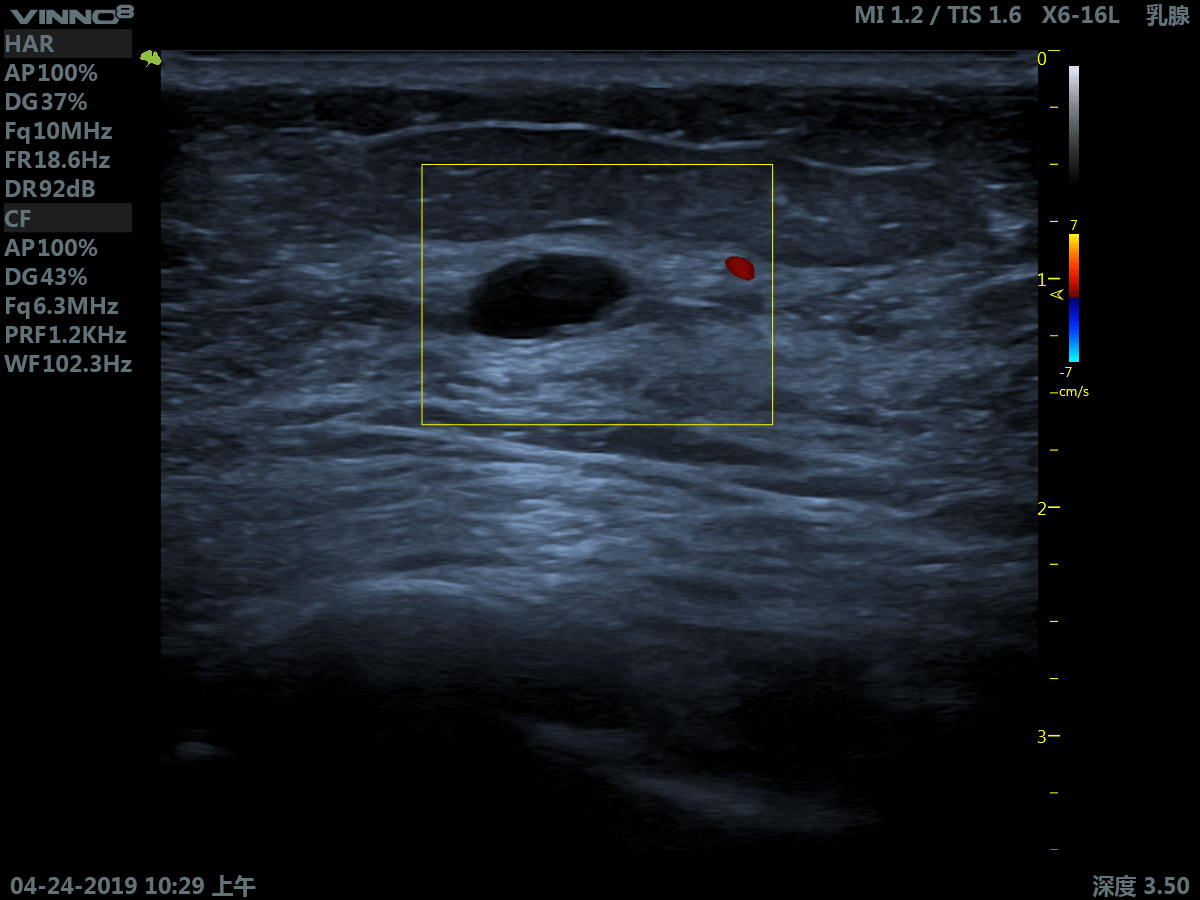

- мелкие объекты (включая щитовидную железу, молочную железу, семенники и т.д.)

10. CFM. Режим цветового допплера

11. CFM+B (B+CF). Комбинированный режим: цветовое допплеровское картирование + В режим